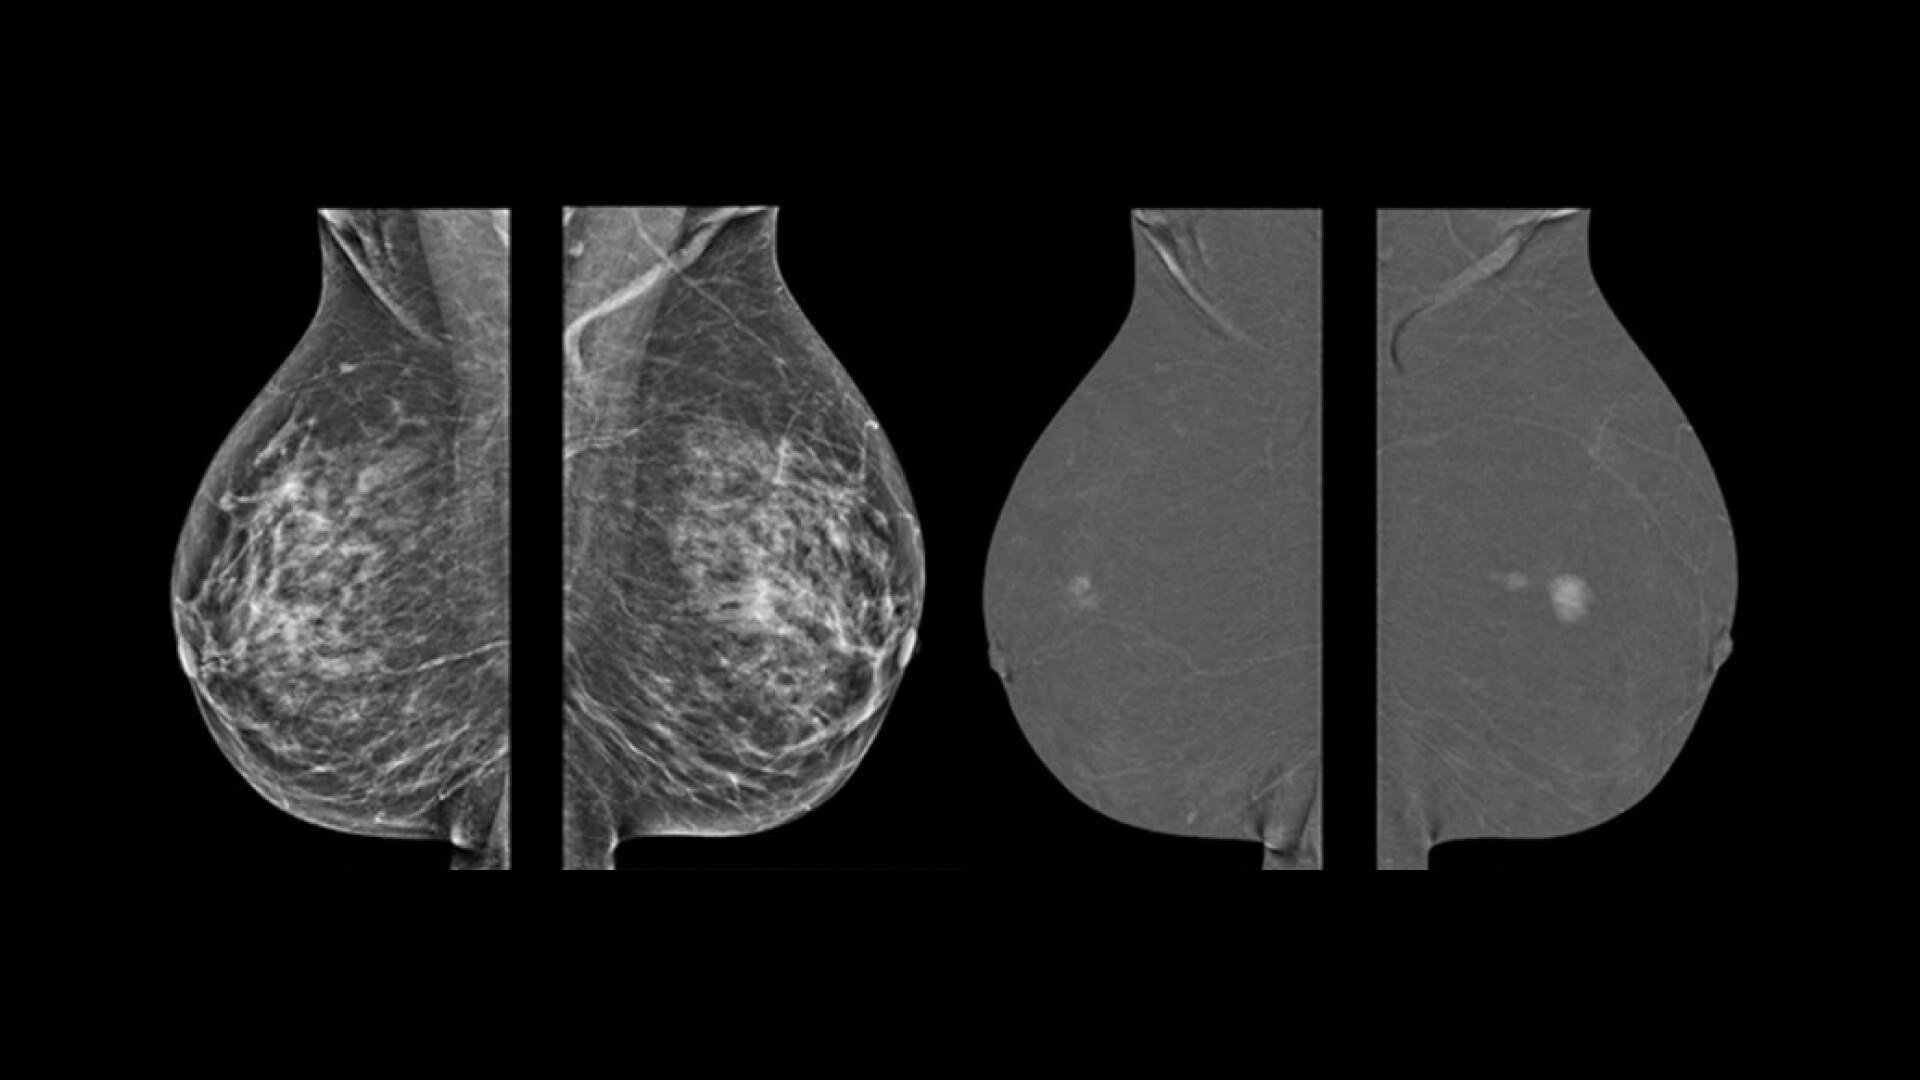

症例が複雑になれば、それだけ不確実な要素も伴います。だからこそ重要になるのは、いかに早期発見し、早期治療に専念できるかどうか。一手先を読み、よりよい未来を的確に見抜く先生方の日々の診断を、Voluson Expert 22の卓越した画質と独自のクリニカルツールがサポートします。

胎児心臓の異常を早期に検出することで、より迅速な介入、分娩計画、予後改善が見込まれます。Voluson Expert 22では、スクリーニング・診断・モニタリングまでトータルにサポートする多彩なツールを取り揃えています。